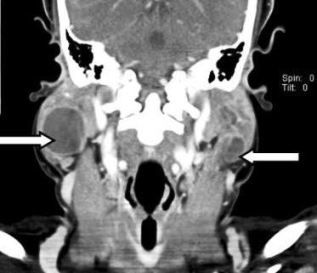

Headaches are a common complaint.